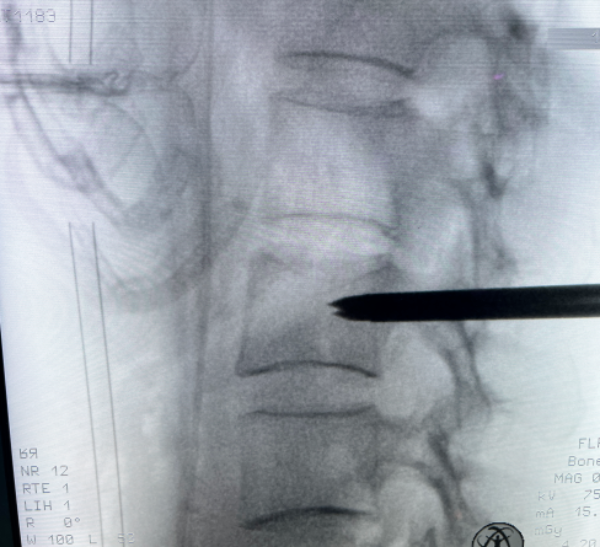

文章配圖

△ 術前MRI:腰2椎體骨質破壞,考慮腫瘤性病變。